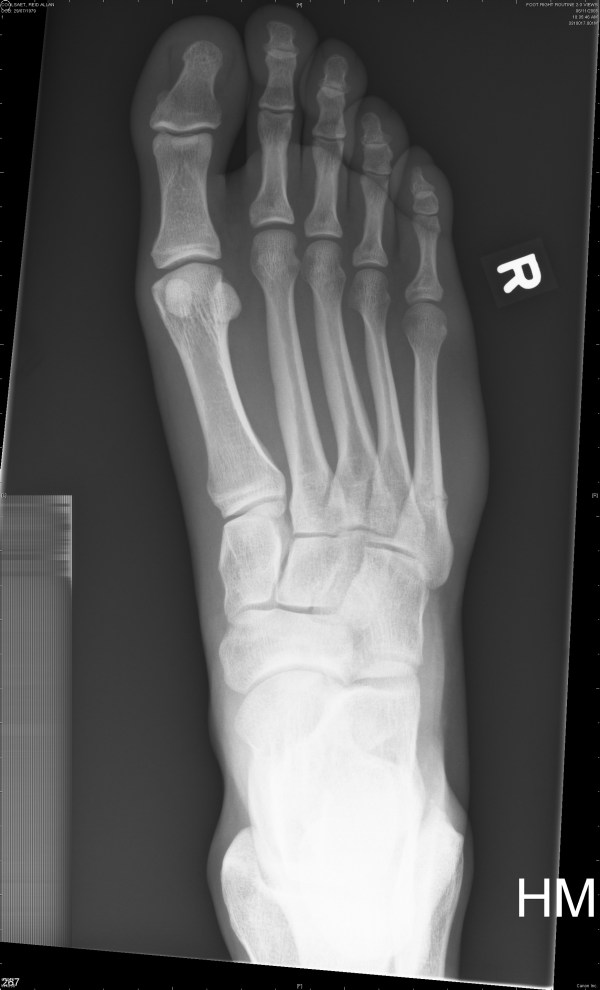

DECEMBER 9TH X-RAY (below)